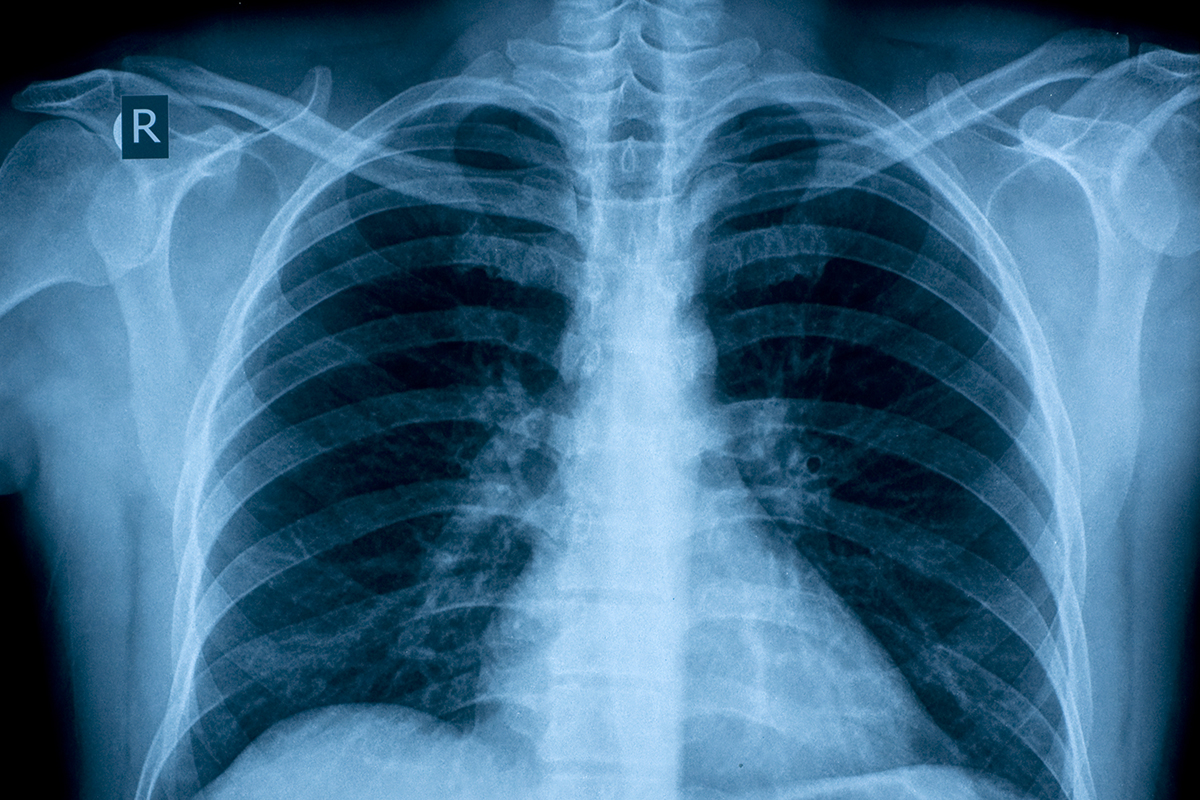

The main difficulty in finding a cure is COPD’s heterogeneous nature – the disease can be thought of as an umbrella term for various symptoms, the most prominent being inflammation of the small airways (bronchitis) and destruction of the air sacs, or alveoli, in the lungs (emphysema). There are also varying genetic and environmental risk factors for COPD, as well as differences in disease exacerbation and progression.

- Also known as emphysema, which is a result of permanently damaged air sacs in the lungs, and chronic bronchitis, which is chronic inflammation of the airways